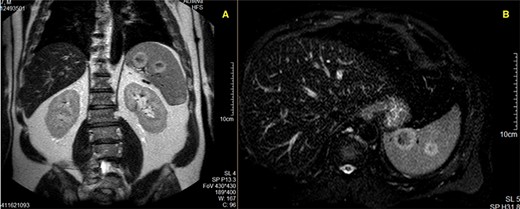

In order to clarify the US findings, an abdominal CT scan was obtained (Fig. 1), which revealed five ring-enhancing nodular lesions 27, 20, 18, 11 and 10 mm in diameter, not clear whether they represent benign or malignant secondary lesions.

CT scan showing two of the five ring-enhancing nodular lesions.